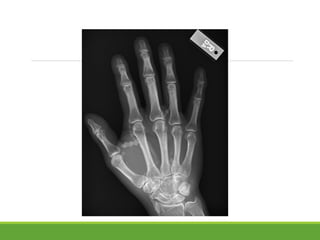

The basic element of an

image is a dot

•Continues dots = a line

•Small dots = high resolution

•Large dots = Low resolution

•Scattered dots = low density, low blackness,

low opacity ( high lucency)

•Close dots = High density, Greater blackness,

High opacity ( low lucency)